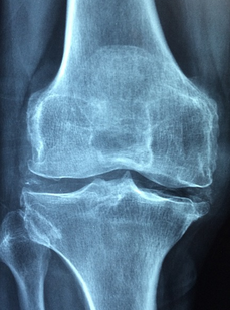

관절염은 관절에 염증이 생기는 질환으로, 통증과 부기, 움직임 제한 등의 증상을 유발합니다. 관절염은 여러 가지 원인과 유형이 있으며, 초기에 적절한 치료를 받지 않으면 관절의 변형이나 기능 손상을 초래할 수 있습니다. 따라서 관절염의 초기 증상을 잘 알고 조기에 대처하는 것이 중요합니다.

관절염의 초기 증상에 대해 알아보겠습니다. 관절염의 초기 증상은 다음과 같습니다.

1. 통증: 관절염의 가장 대표적인 증상으로, 관절 부위에 지속적이거나 간헐적인 통증이 나타납니다. 통증은 운동이나 날씨 변화에 따라 악화되거나 완화될 수 있습니다. 통증은 관절염의 유형에 따라 발생하는 부위나 정도가 다를 수 있습니다. 예를 들어 류마티스 관절염은 작은 관절에서 시작하여 대칭적으로 통증이 나타나고, 골관절염은 체중을 지탱하는 관절에서 통증이 나타납니다.

2. 부기: 관절염에서는 염증 반응으로 인해 관절 주변에 부기가 생깁니다. 부기는 통증과 함께 관절의 움직임을 제한하고 뻣뻣함을 유발합니다. 부기는 열감이나 붉은색으로 변하는 경우도 있습니다. 부기는 주로 염증성 관절염에서 더 심하게 나타납니다.

3. 강직: 관절염에서는 관절의 움직임이 불편하거나 제한되는 증상을 강직이라고 합니다. 강직은 특히 아침에 일어났을 때 더 심하게 나타납니다. 강직은 관절의 연골이 닳아서 윤활액의 분비가 감소하거나, 근육이 위축되거나, 염증으로 인해 발생합니다.

4. 소리: 관절염에서는 관절을 움직일 때 삐걱거리는 소리가 날 수 있습니다. 이 소리는 연골이 닳아서 뼈와 뼈가 마찰하거나, 골극이 생겨서 뼈다극과 충돌하거나, 윤활액의 양이 줄어서 발생합니다.

5. 변형: 관절염에서는 장기간 염증과 퇴행이 지속되면 관절의 모양이나 위치가 변형될 수 있습니다. 변형은 주로 골관절염에서 나타나며, 굽은 다리, O다리, 손가락 마디의 돌출 등으로 나타납니다.